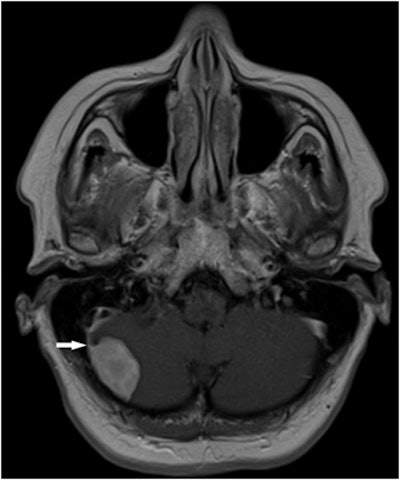

Meningioma seen at whole-body MRI in a 43-year-old man who underwent surgery. Image courtesy of Dr. Andrzej Cieszanowski.Type III findings included one brain glioma, one bronchogenic carcinoma, one renal cell carcinoma, one complicated renal cyst, one ovarian tumor, one testicular Leydig cell tumor, and metastases to the lung, liver, and adrenal gland in one patient, Cieszanowski said. Benign lesions classified as type III included a meningioma.